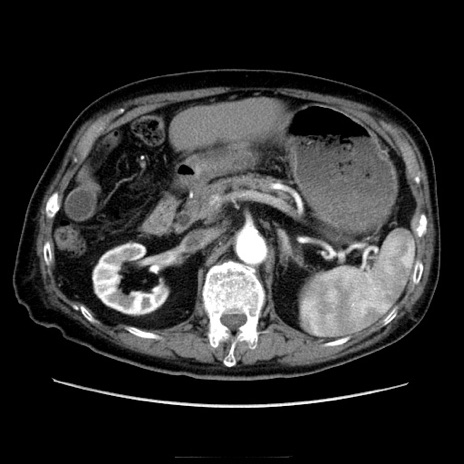

症例21(横断像)

【症例】70歳代男性

【主訴】腹痛

【現病歴】肝硬変・肝細胞癌にてかかりつけの方。約9時間前に食後より腹痛出現。症状が徐々に増悪し、嘔吐出現したため来院。

【既往歴】肝硬変、肝細胞癌(RFA、TACE後)

【身体所見】意識清明、表情苦悶様、BT 36℃、BP 129/78mmHg、P 88bpm、SpO2 97%(RA)、右上腹部から心窩部にかけて圧痛あり、反跳痛なし、筋性防御あり。

【データ】WBC 5800、CRP 0.16